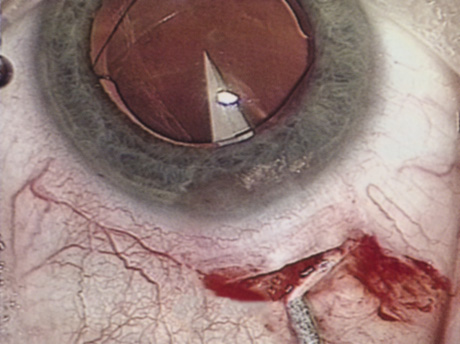

HYDRODISSECTION

Hydrodissection can be performed after the surgeon has successfully completed capsulorrhexis.97 If the capsulorrhexis is not intact, fluid forced around the interior of the capsule may cause the bag to splay open. With capsulorrhexis, hydrodissection is a safe and extremely useful maneuver. Hydrodissection can be thought of as two maneuvers: hydrodelineation and cortical cleaving hydrodissection. By placing a 27-gauge cannula on a syringe filled with balanced saline solution (BSS), the surgeon can direct fluid beneath the residual anterior capsular rim to create a cleavage plane. Depending on the direction the fluid wave takes, different lamellae of the cataract will be separated. Hydrodelineation is the term used when the cleavage plane separates the adult nucleus from the fetal nucleus or the adult nucleus from the more peripheral epinucleus. Hydrodelineation often results in the characteristic golden ring sign (Fig. 11). Cortical cleavage occurs when the cortex is separated from the capsular bag (Fig. 12). Finding the cortical cleavage plane may be facilitated by gently lifting the capsular margin away from the cortex with the BSS cannula before injecting. Several small bursts of fluid allow the surgeon to monitor progress of the fluid wave. When dealing with a soft nucleus, the authors strive to perform true cortical cleaving hydrodissection. For a hard nucleus, hydrodelineation allows manipulation of less of the nuclear bulk, although the remaining epinuclear shell must be addressed in an additional step. Hydrodelineation is particularly useful if the nucleus is not freely mobile after cortical cleaving hydrodissection.

Fig. 11. A crisp “golden ring” is seen from the fluid cleft between the epinucleus and nucleus with hydrodelineation.

Fig. 12. Hydrodissection, performed subincisionally with a 27-gauge J-cannula, produces a cleavage plane between the capsule and the cortex. The small blue arrows indicate the advancing fluid wave.